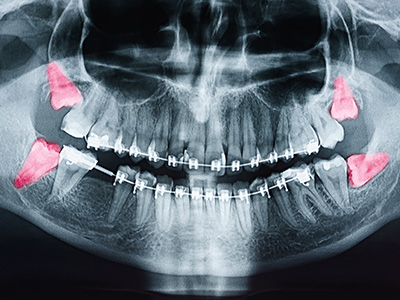

Imaging plays a central role in modern assessment. Standard panoramic X-rays give a broad view of the jaws, while cone-beam computed tomography (CBCT) or similar 3D imaging can clarify root shape, depth of impaction, and the relationship to critical structures such as the inferior alveolar nerve and sinus cavities. This level of detail helps clinicians anticipate potential complications and plan a precise, conservative approach.

Imaging is essential for precise assessment: panoramic X-rays show overall jaw relationships, while cone-beam computed tomography (CBCT) or other 3D imaging clarifies root anatomy, depth of impaction and proximity to structures like the inferior alveolar nerve or sinuses. This information allows clinicians to estimate risk and choose the safest, most effective approach.